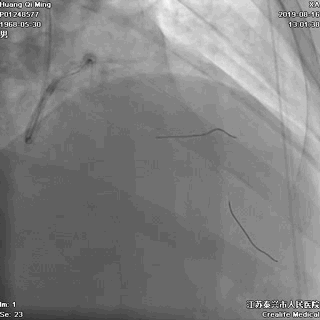

冠状动脉造影

右冠状动脉无严重狭窄

左主干前分叉处血管正常

LCX近中段病变,狭窄最重达90%

LAD中远段血管偏细,弥漫性病变,狭窄达90%

导丝通过病变

球囊扩张,PTCA

导丝通过病变抵达血管远段

8atm,2.0*20球囊行PTCA